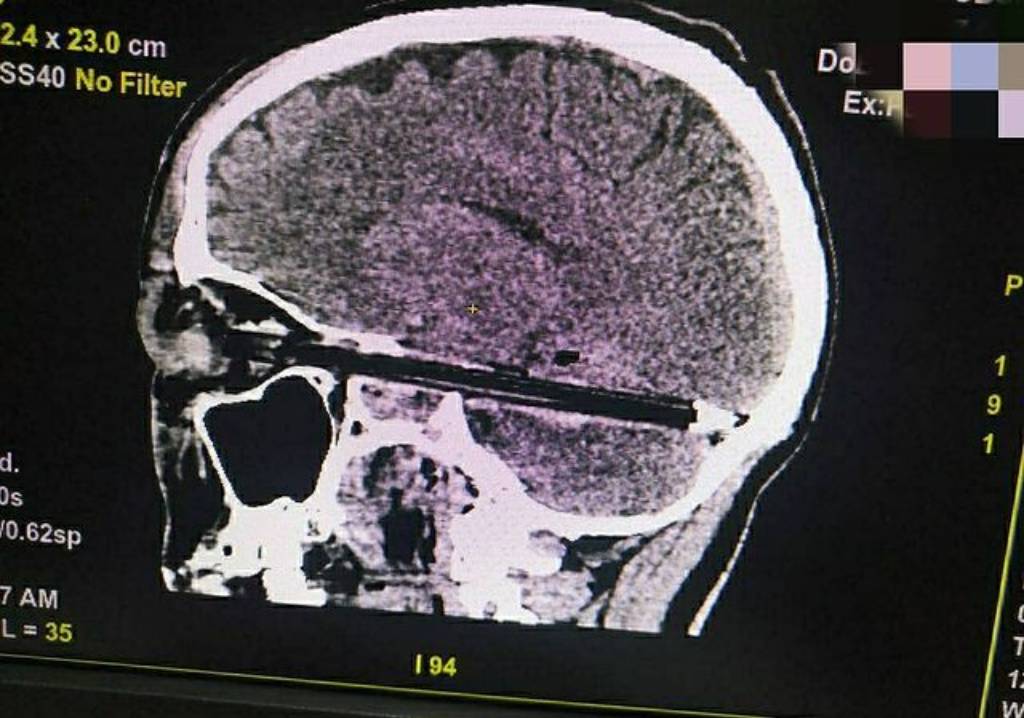

По данным , мужчина был доставлен из СИЗО-3 в городскую больницу с шариковой ручкой, которая прошла через глаз и мозг. В областном ГУФСИН агентству пояснили, что он получил травму 5 февраля на территории изолятора, где содержался. Со слов обвиняемого, повреждения он якобы нанёс себе сам в состоянии нервного срыва.